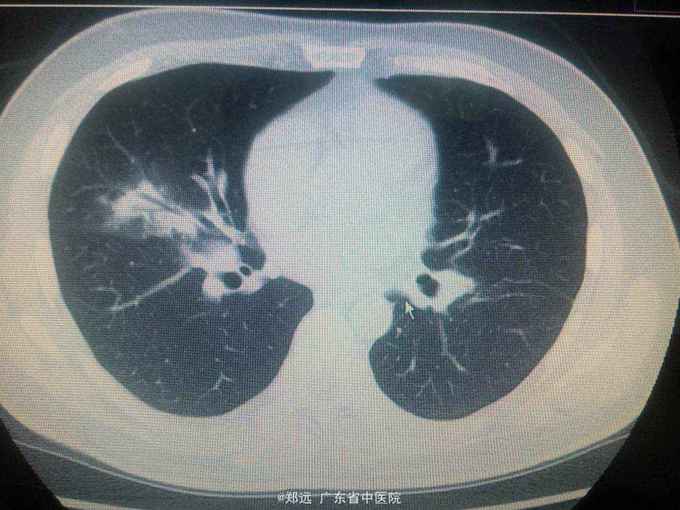

体查:双下肺湿啰音。三尖瓣区3/6级收缩期杂音。 胸部ct:双肺斑片结节影并空洞形成,左胸少量积液。血色素88克/升,白细胞11.48,中性粒81.3%,降钙素原14.84,ALT 121,AST 134.超声提示三尖瓣赘生物,三尖瓣大量返流。血培养金葡菌。

诊断:急性感染性心内膜炎,脓毒症,肺脓肿,丙型肝炎。 治疗:入院予万古霉素0.5克q6h,经治疗五日血象正常,降钙素原1.54,但仍反复高热,考虑肺脓肿合并阴性菌感染,加用头孢哌酮舒巴坦3克q12h,治疗五日仍有发热,血培养阴性,白细胞正常,降钙素原0.15,头孢哌酮舒巴坦改为美罗培南0.5克q8h,两日后无再发热,维持该方案至治疗四周后改予万古霉素0.5克q8h加美罗培南0.5克q12h继续治疗两周,复查超声提示三尖瓣熬生物较入院时缩小约三分之一,多次血培养阴性,胸部ct提示肺部炎症明显吸收予出院。出院后患者仍间发热,出院后约七周再次返院,查白细胞13.88,中性粒65.9%,血色素正常,降钙素原0.55,血培养提示溶血葡萄球菌,胸部ct示双肺多发感染灶,较前吸收,胸腔积液已吸收。予原万古霉素加美罗培南方案治疗,两日后无发热,治疗三周后多次血培养阴性,胸部ct提示肺部感染基本吸收,行三尖瓣赘生物切除并三尖瓣修补术,术中见三尖瓣后瓣瓣叶破坏严重,赘生物大小约2*1厘米。术后恢复良好,维持万古霉素加美罗培南治疗一周后改予万古霉素0.5克q8h加阿米卡星0.4克q12h治疗两周,赘生物及多次血培养阴性予出院。